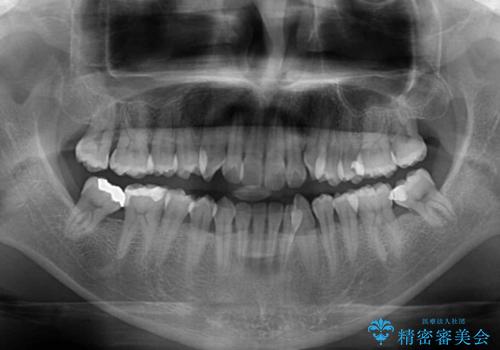

上顎の歯列弓が下顎に対して狭いため、臼歯のかみ合わせがが咬頭対咬頭の状態です。

上顎の急速拡大装置を使用して、上顎骨を側方に拡大することで上顎歯列弓を拡大し、それに伴い下顎歯列弓も拡大できるようにして、歯列を整えていくこととしました。